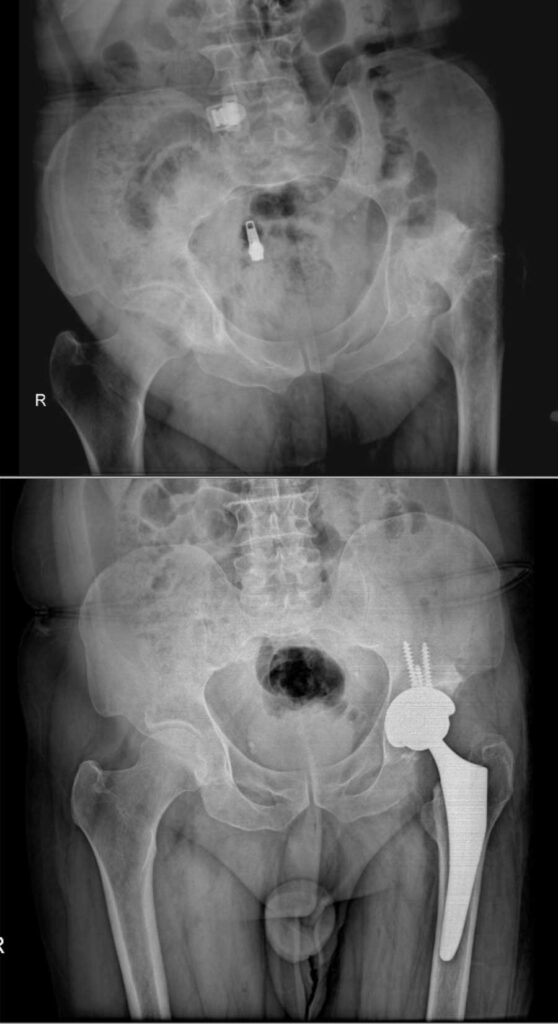

عکس تعویض مفصل لگن

برای آشنایی با تصاویر واقعی رادیوگرافی لگن قبل و بعد از جراحی، عکس تعویض مفصل لگن چند بیمار در زیر وجود دارد. با کلیک بر روی هر کدام از آنها تصویر بزرگتر و کامل را خواهید دید.